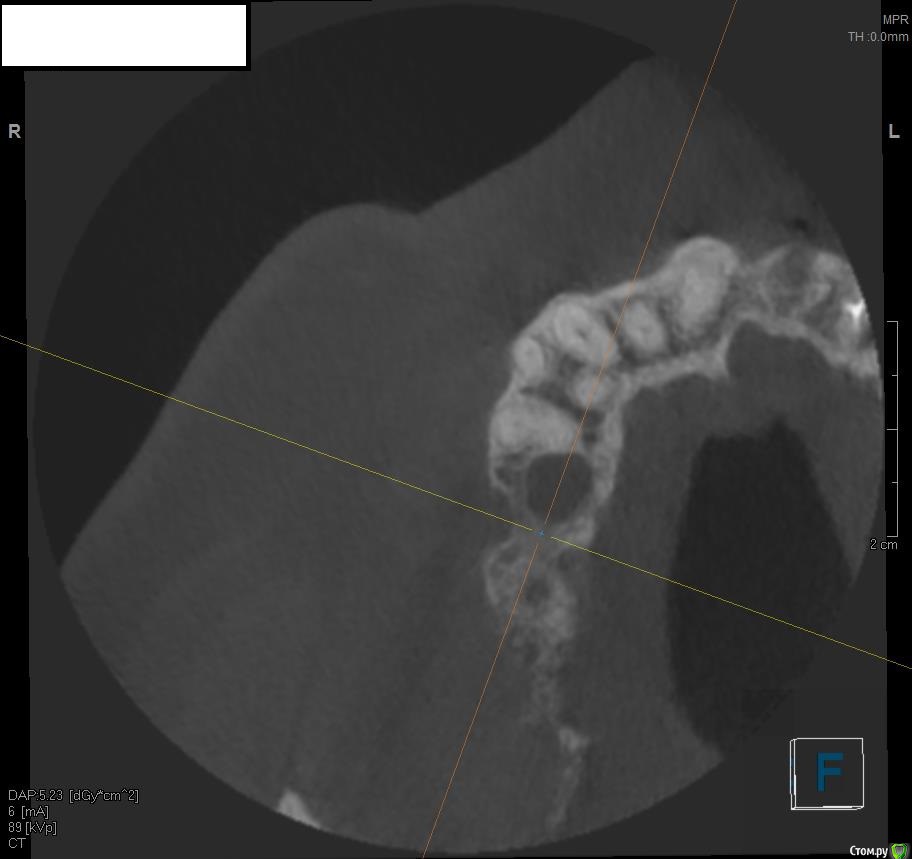

Jurai Опубликовано 19 мая, 2016 Поделиться Опубликовано 19 мая, 2016 Вот такой пациент: Больше года назад выполнена радикальная гайморотомия, с созданием соустья по поводу изменений слизистой в синусе. Сейчас картина такая. Ортопед желает два имплантата, а я что-то в сомнениях - платформы на уровне апексов меня не привлекают. Прошу вашего мнения, что возможно здесь сделать? По поводу непрозрачности синуса - ЛОР дает добро. Ссылка на комментарий

ILGAMSA Опубликовано 19 мая, 2016 Поделиться Опубликовано 19 мая, 2016 Вот такой пациент: Больше года назад выполнена радикальная гайморотомия, с созданием соустья по поводу изменений слизистой в синусе. Сейчас картина такая. Ортопед желает два имплантата, а я что-то в сомнениях - платформы на уровне апексов меня не привлекают. Прошу вашего мнения, что возможно здесь сделать? По поводу непрозрачности синуса - ЛОР дает добро.Бардак.Нужна консультация ЛОР-врача, владеющего FESS. Лучше было бы удалить 15, после заживления растить кость по вертикали, опираясь от костного пика 14 зуба. Да и в остальном наладить гигиену, разобраться с остальными. 1 Ссылка на комментарий

Nazim_NV86 Опубликовано 19 мая, 2016 Поделиться Опубликовано 19 мая, 2016 Синус заполнен. Отправьте на эндоскопическую микрогайморотомию. Ссылка на комментарий

TIGER Опубликовано 20 мая, 2016 Поделиться Опубликовано 20 мая, 2016 А такую пазуху тоже сначала лучше санировать через лор ?однозначно,там синусит 2 Ссылка на комментарий